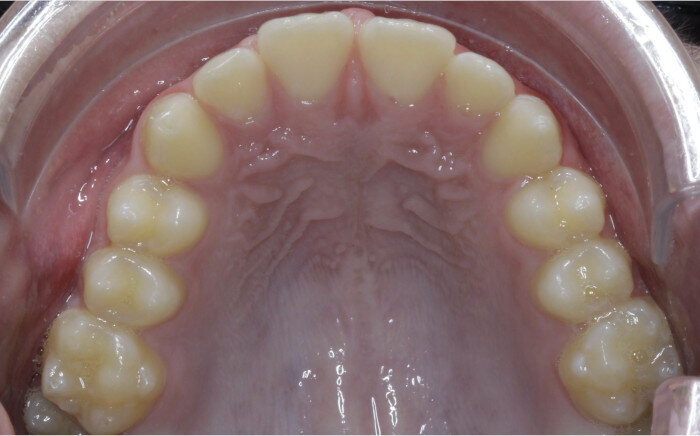

Case 5: Skeletal expansion

In cases where absolute maxillary expansion is desired with little to no dental side effects, maxillary anchorage with TADs is a wonderful solution. This allows for sutural expansion that has little to no dental compensation. Many designs exist for TAD placement with expansion. In some cases, a tissue-borne expander is used with no anchorage on the molars. This is typically used to encourage the maximum amount of skeletal expansion when dental tipping is undesired (Figs. 52 & 53). In cases where molar anchorage is desired, a banded approach can be used in conjunction with TADs (Figs. 54–59).

Fig. 52

Fig. 53